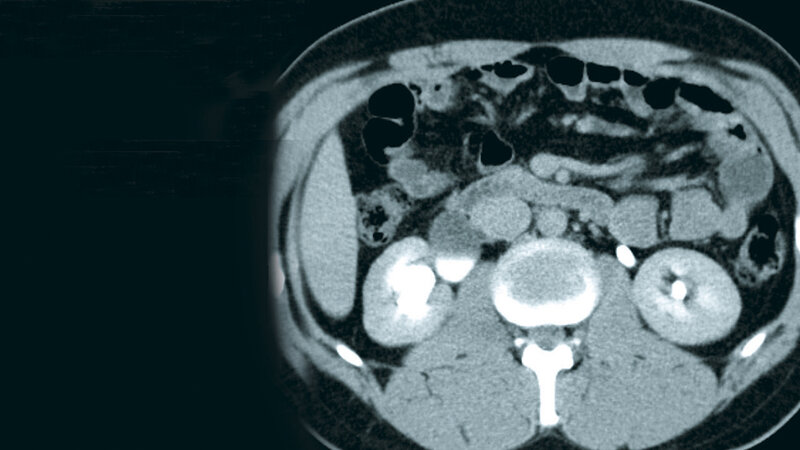

Schlüsselwörter: LWS, CT, MRT, Harnabflussstörung

Keywords: Lumbar spine, CT, MRI, urodynamic disorder